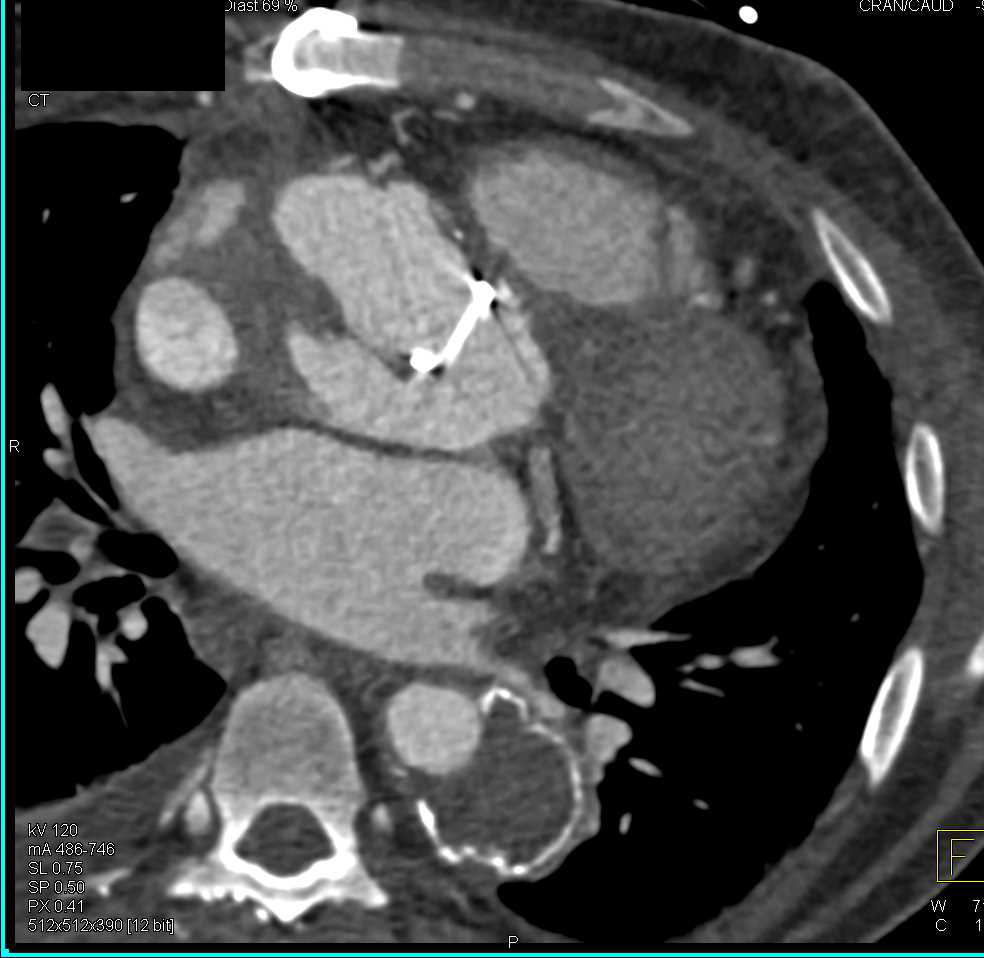

Tumor Infiltrates the Posterior Mediastinum and Encases the Aorta